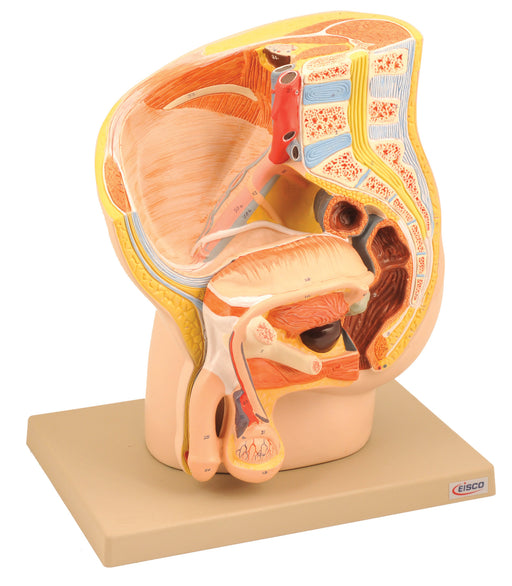

Model, Male Pelvis

Life Size 2 parts 12"h x 6"w x 10" l Median section of the male pelvis represents the internal structures of the male urological an...

View full detailsAM119BAS -